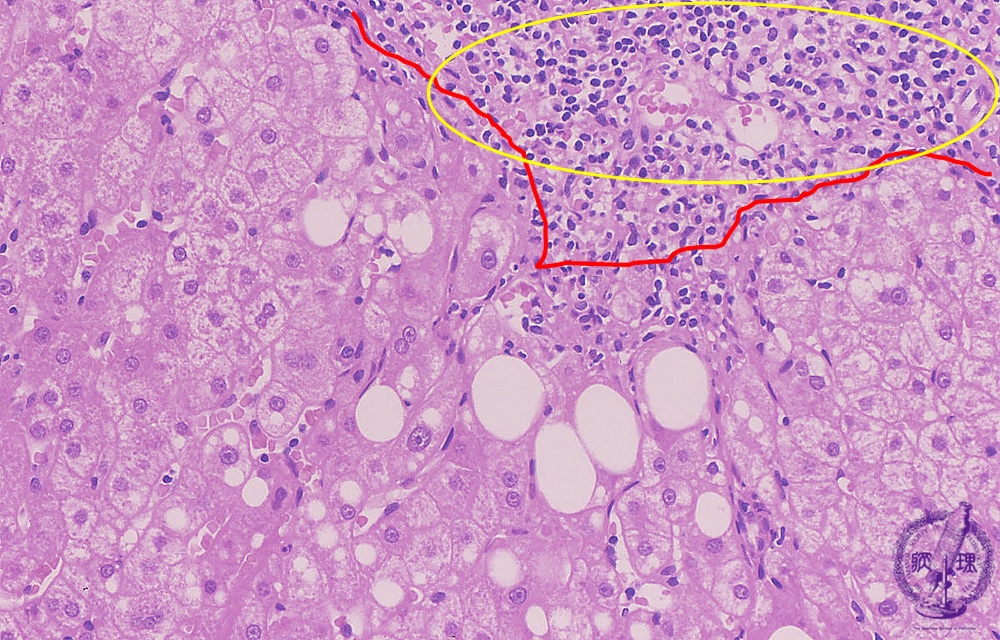

Microscopic image (HE stain, high power view): There is dense portal chronic inflammation with interface hepatitis comprising lymphocytic inflammation at the limiting plate and concurrent hepatocellular drop-out (yellow box). Hepatocytes contain large cytoplasmic lipid droplets (steatosis).